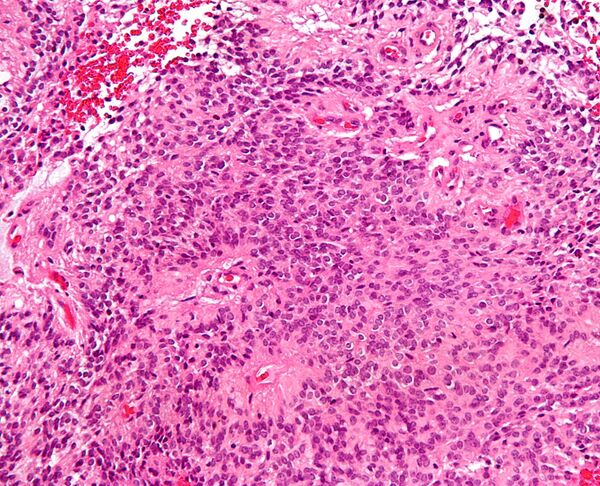

Периваскулярные псевдорозетки состоят из спицевидных структур с конусообразными клеточными отростками, расходящимися вокруг стенки расположенного в центре сосуда. Приставка «псевдо» показывает различие этих розеток от розеток Гомера Райта и Флекснера-Винтерстайнера, потому что центральная структура розетки фактически не формируется самой опухолью, а вместо этого представляет собой нативную, неопухолевую ткань. Кроме того, некоторые ранние исследователи спорили об природе центрального просвета, выбирали приставку «псевдо», чтобы указать, что центр не является истинным просветом, а содержит гистологические структуры.[2]

Периваскулярные псевдорозетки встречаются в большинстве эпендимом независимо от степени злокачественности или варианта. Они значительно более важны для диагностики эпендимомы, чем истинные эпендимальные розетки. Но к сожалению, периваскулярные псевдорозетки менее специфичны — они также встречаются в медуллобластомах, PNET, центральных нейроцитомах и, реже, в глиобластомах, а также в редких детских опухолях, мономорфных пиломиксоидных астроцитомах.[2]